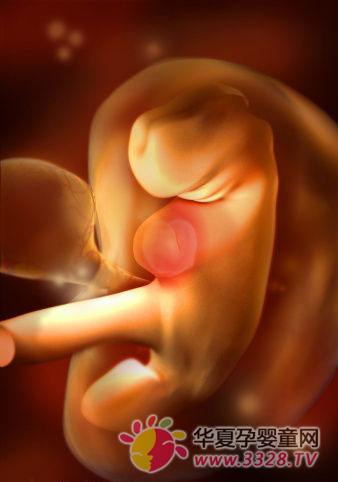

怀孕两个月胎儿图

胎儿发育全过程图